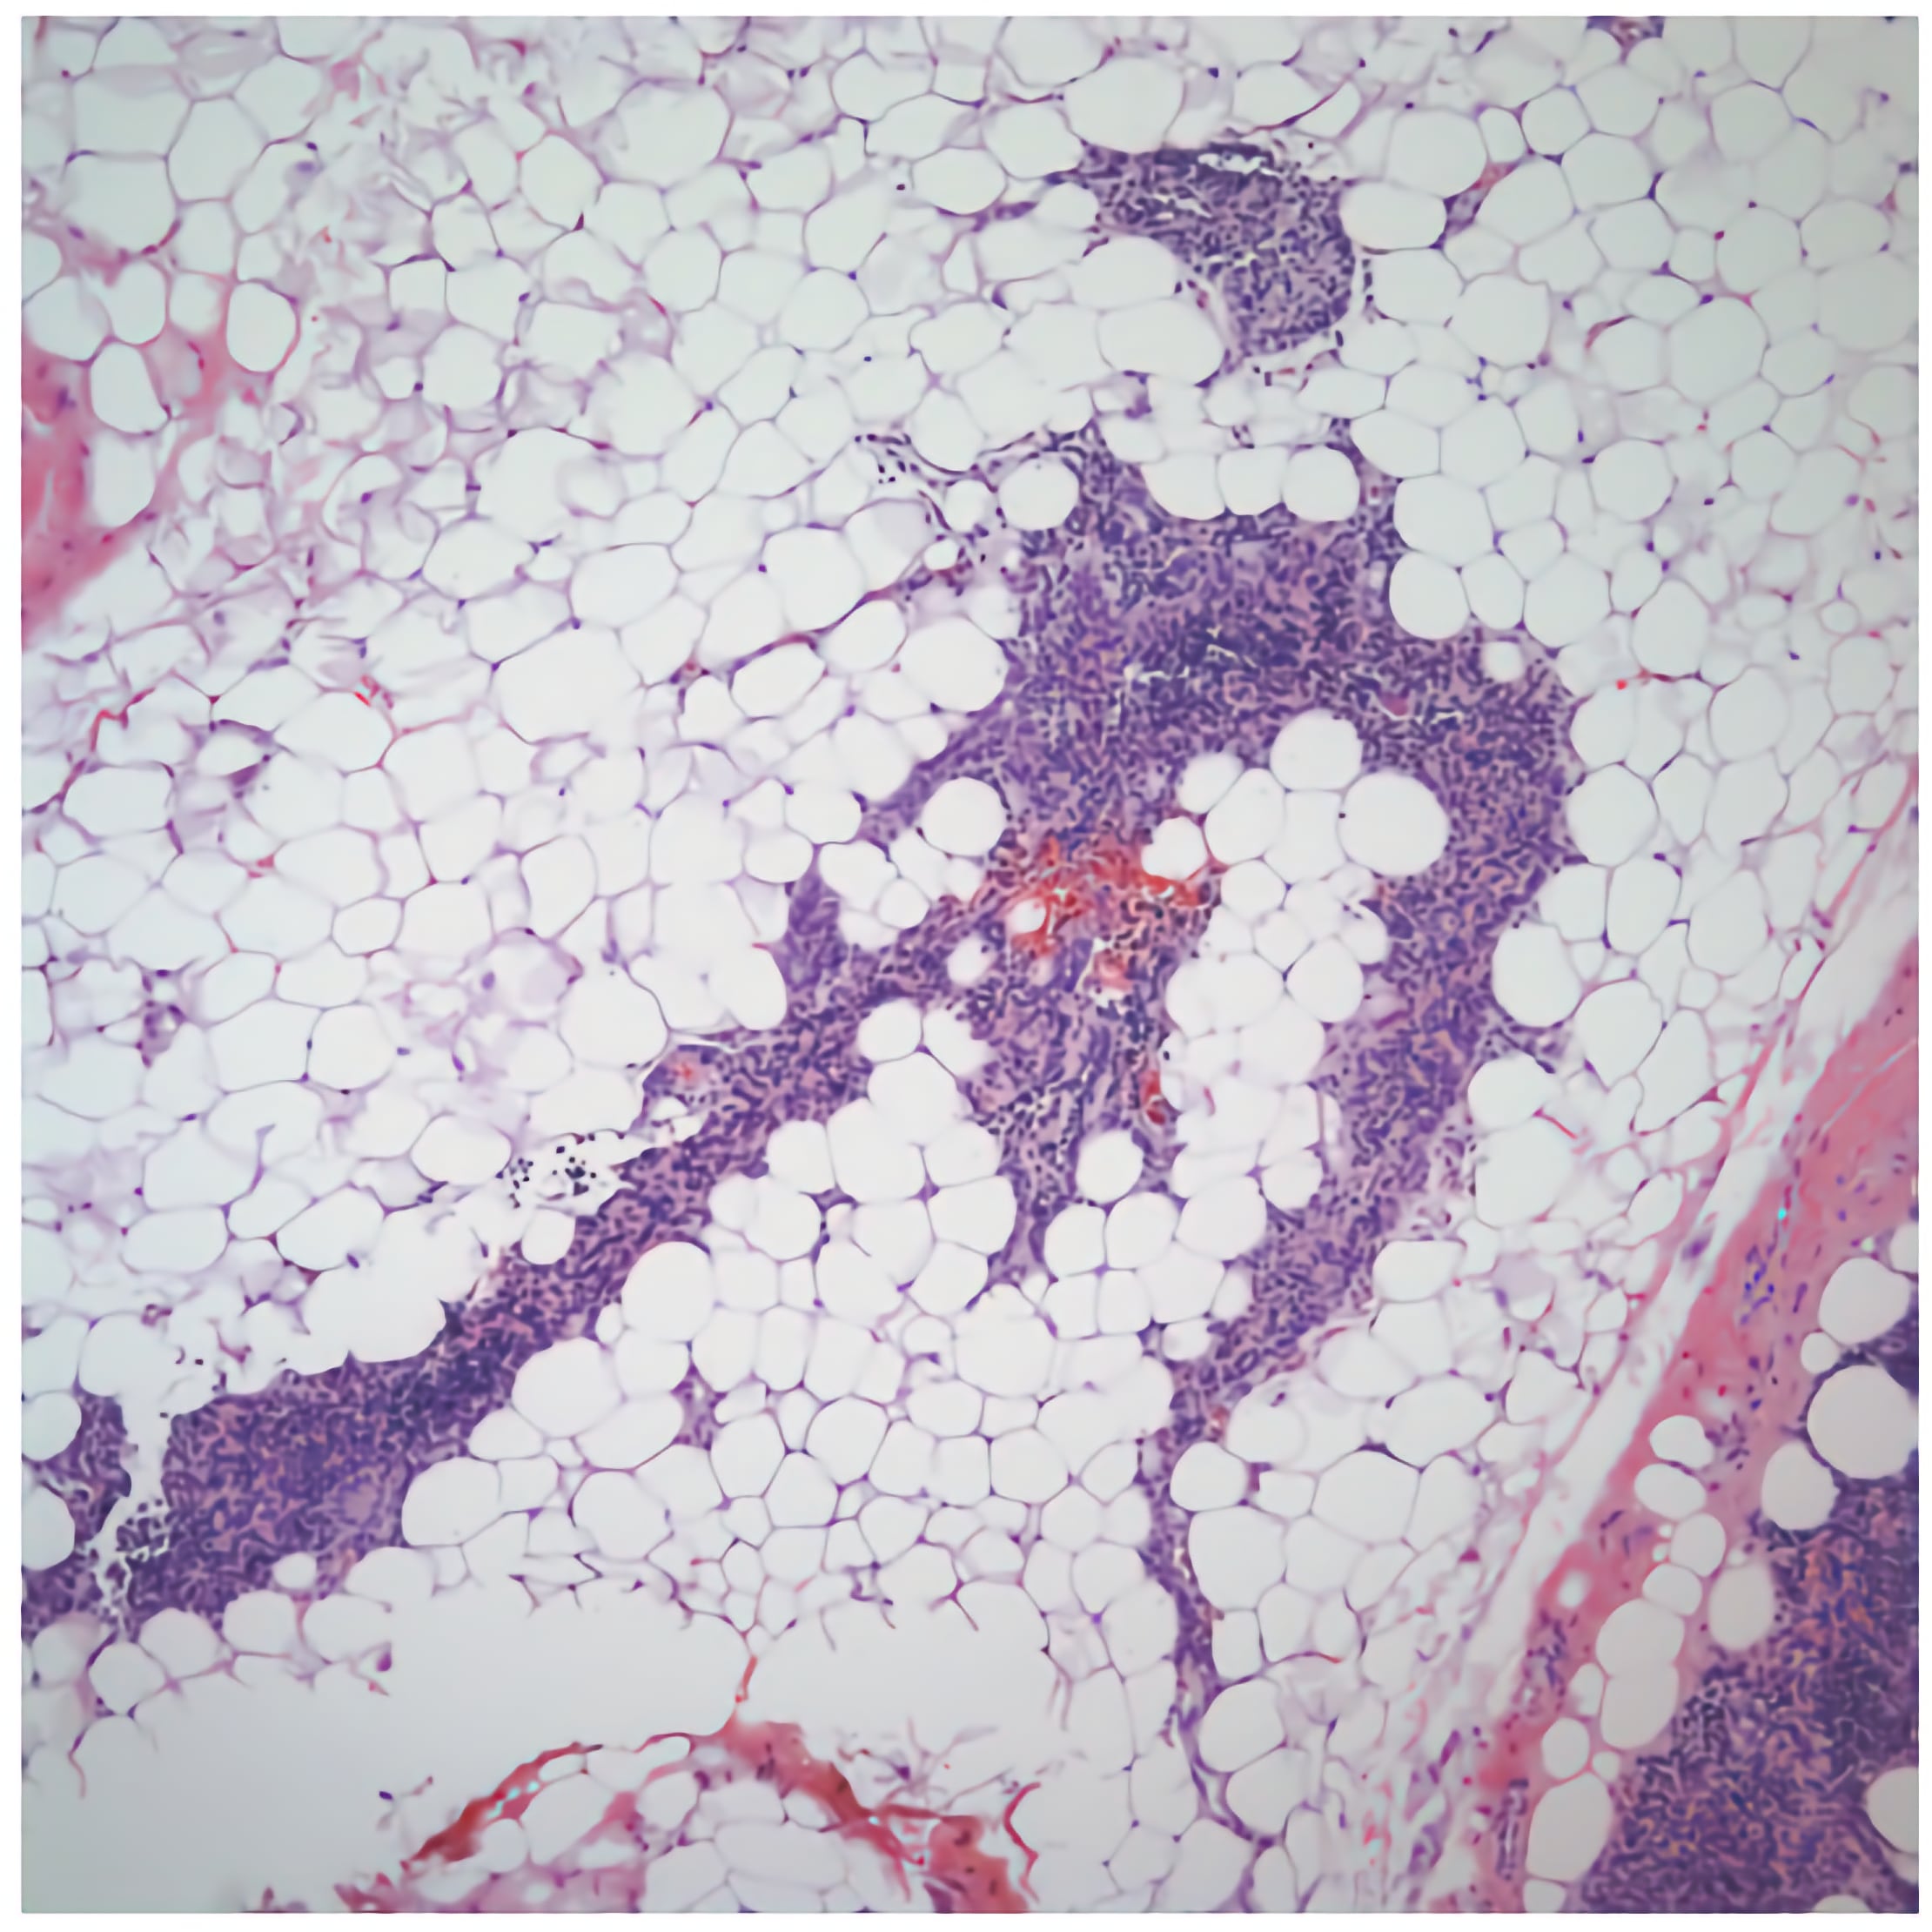

The thymus becomes active in neonates and remains active throughout childhood until puberty when the thymus begins to involute. During involution, the number of thymocytes decreases and production of T-cells slows. Adipose tissue replaces thymocytes until most of the thymus is composed of adipose tissue.